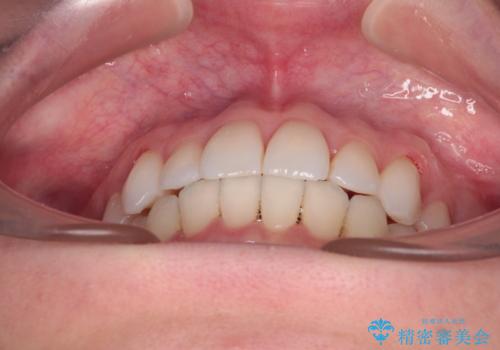

【モニター】インビザラインで気になるデコボコと八重歯をきれいに整える

- 上下前歯のデコボコ、特に右上の八重歯を気にして来院された患者様です。

治療後半では悪阻によりマウスピースの装着時間が不十分となることもありましたが、それよりも前にしっかりと装着時間を守って治療を進めることができたため、特に気になるところなく治療を終えることができました。